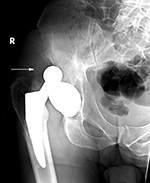

Left hip unipolar prosthesis (hemiarthroplasty) dislocation |

Most hip arthroplasty dislocations are posterior. From Benjamin, 1994 |